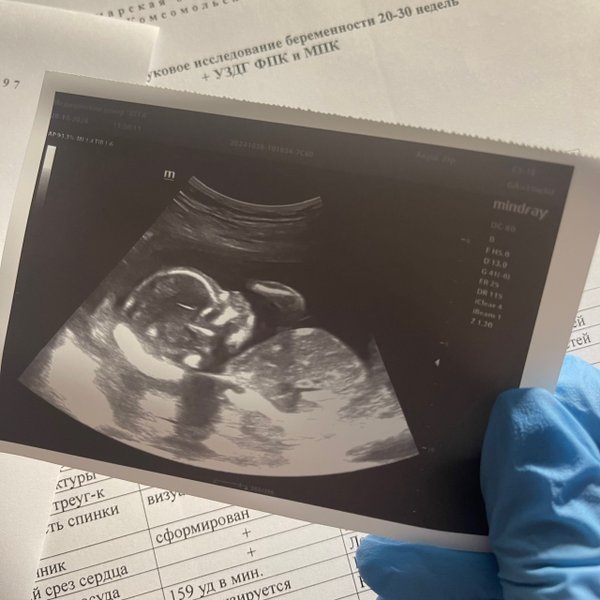

Кажется, еще вчера тест показал две полоски, а сегодня мы уже рассматривали ручки и ножки на мониторе ВАШЕ крошечное солнышко‼️ PS.. группа поддержки в виде ️бабушки и мужа на осмотре . были --- Бородулина Наталья (Врач УЗИ, Косметология) (08.01.2026): Давайте поиграем‼️ Угадайте по фото #УЗИ, кто тут ( Шутка, конечно, рано еще Но верить в чудеса можно уже сейчас). Поделитесь в комментариях своими первыми #фото «горошков», «фасолинок» и «эмбриончиков» устроим галерею самого начала жизни ️

PS.. группа поддержки в виде ️бабушки и мужа на осмотре . были

Бородулина Наталья (Врач УЗИ, Косметология) (08.01.2026):

Давайте поиграем‼️

Угадайте по фото #УЗИ, кто тут ( Шутка, конечно, рано еще Но верить в чудеса можно уже сейчас).

Поделитесь в комментариях своими первыми

#фото «горошков», «фасолинок» и «эмбриончиков» устроим галерею самого начала жизни ️